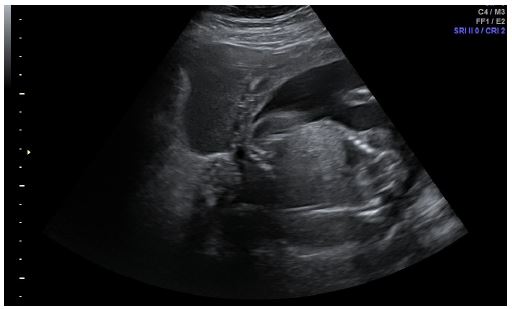

A trans-abdominal ultrasound scan performed by a level II ultrasound practitioner which was reported as ‘There is ascites with echogenic material, likely proteinaceous in nature. There is no evidence of gallstones or cholecystitis. The aorta, spleen, kidneys and pancreas appeared normal; however the appendix could not be visualised (Figure 1).

Figure 1: Transabdominal ultrasound showing intra-abdominal mixed echogenic fluid.

Finally, a bedside trans-abdominal ultrasound scan by a level III gynaecological ultrasound practitioner was requested. This was reported as:'There is a significant volume of mixed echogenic free fluid in the abdominal cavity in keeping with blood. The right ovary contains a 10 mm well demarcated cystic structure containing mixed echogenic material with a breach of the ovarian serosa suggestive of cyst rupture’.